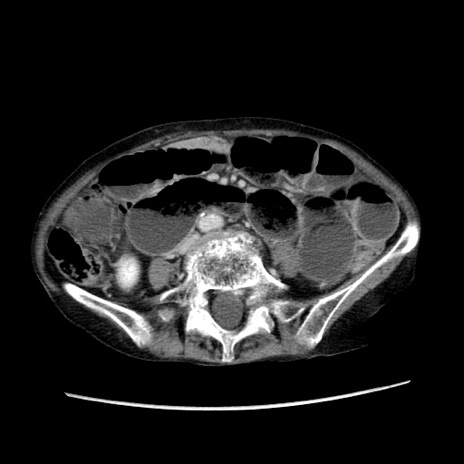

症例25(横断像)

【症例】80歳代女性

【主訴】胸のつかえ感

【現病歴】約9時間前に食後から胸のつかえた感じあり、嘔吐あり、来院。

【既往歴】胃癌(全摘)、胆摘、虫垂炎

【身体所見】心窩部に圧痛あり、反跳痛なし。

【データ】WBC 5700、CRP 0.05